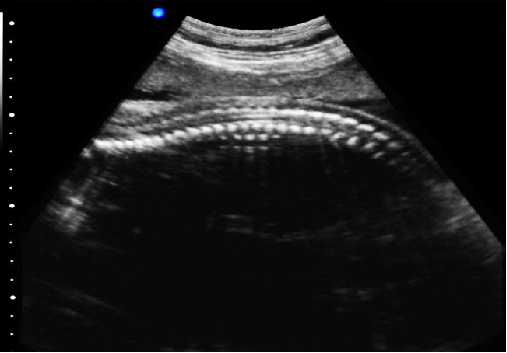

脊椎檢查:

脊柱裂的預(yù)防和確診,一般在動(dòng)物懷孕以后定期給動(dòng)物做超聲檢查,通過(guò)超聲、超聲檢查可以早期發(fā)現(xiàn)動(dòng)物胎兒是否合并了脊柱裂或是神經(jīng)管閉合不全。